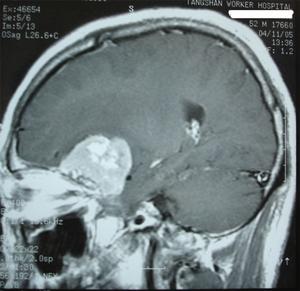

5.CT和MRI掃描 可確定腫瘤的部位和大小,絕大多數可作出定性診斷。CT掃描示邊界清晰的均勻高密度影,增強後顯著。少數呈混合密度或低密度改變。MRI見腫瘤多數呈等信號,增強後明顯強化。

2.MRI掃描 MRI對診斷本病是有意義的MRI可以顯示腫瘤與蝶骨翼和眼眶的關係骨質破壞情況等。尤其是對內側型的蝶骨嵴腦膜瘤MRI還可以提供腫瘤與頸內動脈的關係有時腫瘤將頸內動脈包裹在內或腫瘤附著在海綿竇上這些情況對手術切除腫瘤均有重要的參考價值增強後的MRI圖像更清晰。